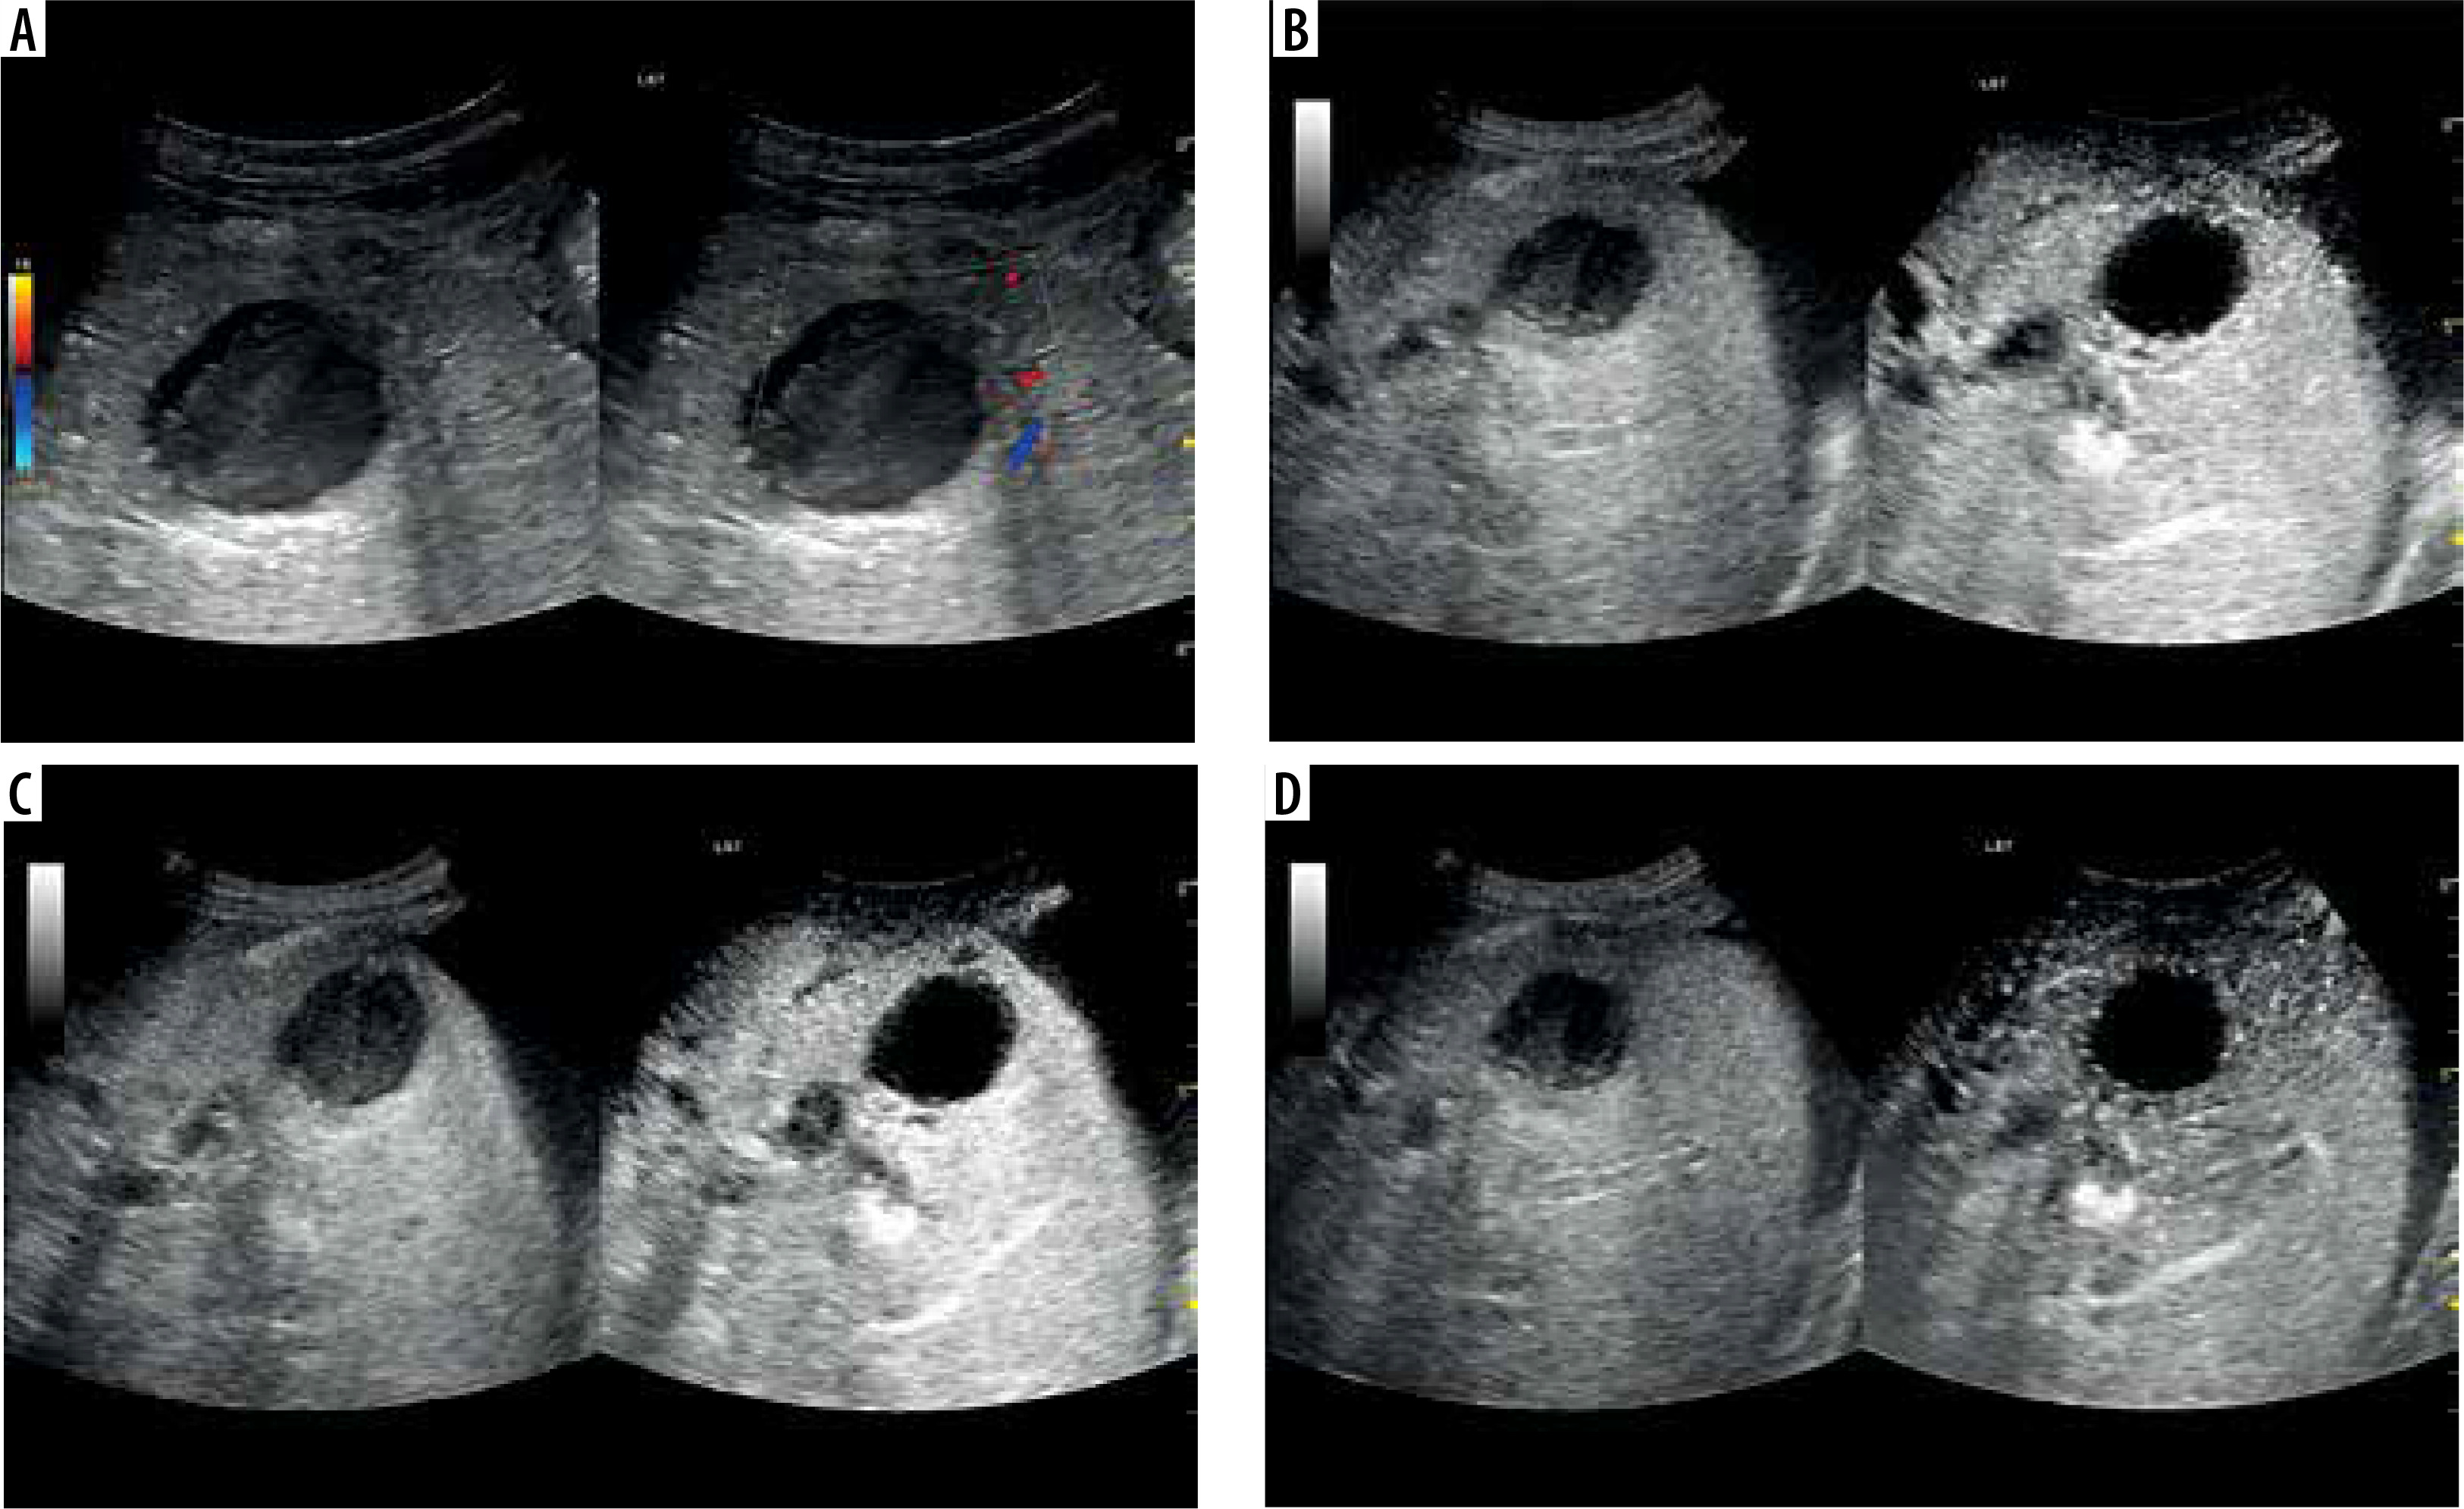

Figure 7

A) Ultrasound and color Doppler: transverse view shows focal lesion in right liver lobe, classified as type IV abscess via CT. Lesion echogenicity lower than liver, visible liquid part and zone of edema. B) CEUS arterial phase: abscess capsule clearly visible, undergoing intense contrast enhancement. C) CEUS portal phase: wash-out effect visible from abscess capsule, fluid component unchanged. D) CEUS late venous phase: further wash-out effect visible; abscess capsule enhancement less intensive compared to liver parenchyma; type IV pattern confirmed with visible liquid component throughout phases